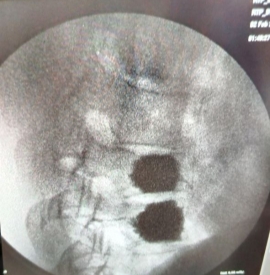

Из исследования исключили осложненные травмы позвоночника, переломы задних опорных структур, травматические грыжи дисков. Травма имела подострый или хронический период с болевым синдромом, усиливающимся при физической нагрузке ноющего характера. УКД в среднем 18,8±9 0 градусов. Степень компрессии тел позвонков составила в среднем 35,2±9 %. Основной причиной травмы оказались падение с высоты и автотравма. Имел место перелом 2 пациентам выполнена вертебропластика позвонка (рис. 2).

Рис. 2. Компрессионный перелом Тн11 позвонка с выполнением вертебропластики Тн11 и Тн12 позвонков. Угол кифотической деформации сохранен до 15 градусов по УКД, компрессия 1 степени

Выбор хирургического вмешательства с ориентацией только на степень компрессии в нашем материале себя не оправдала. Требовалось учитывать кифотический угол, степень остеопороза. Выполнение вертебропластики (рис. 2 вертебропластика) не купировали болевой синдром. Причиной неэффективность вертебропластики у пациентов молодого и среднего возраста нами рассматривалась либо как боли с сочетанного сегмента [7], либо увеличение угла кифотической деформации [2].